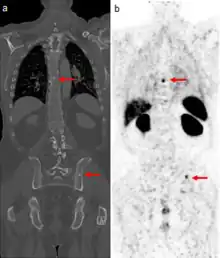

The extent of cancer spread is assessed by MRI or PSMA scan – a positron emission tomography (PET) imaging technique where a radioactive label that binds the prostate protein prostate-specific membrane antigen is used to detect metastases distant from the prostate.[30][24] CT scans may also be used, but are less able to detect spread outside the prostate than MRI. Bone scintigraphy is used to test for spread of cancer to bones.[30]